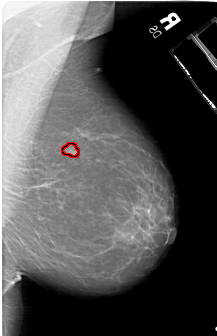

A_1177_1.RIGHT_CC

RIGHT_MLO LINES 6376 PIXELS_PER_LINE 4111 BITS_PER_PIXEL 12 RESOLUTION 43.5 OVERLAY

FILE: A_1177_1.RIGHT_MLO.OVERLAY

TOTAL_ABNORMALITIES 1

ABNORMALITY 1

LESION_TYPE MASS SHAPE LOBULATED MARGINS OBSCURED

ASSESSMENT 3

SUBTLETY 4

PATHOLOGY BENIGN

TOTAL_OUTLINES 1

BOUNDARY